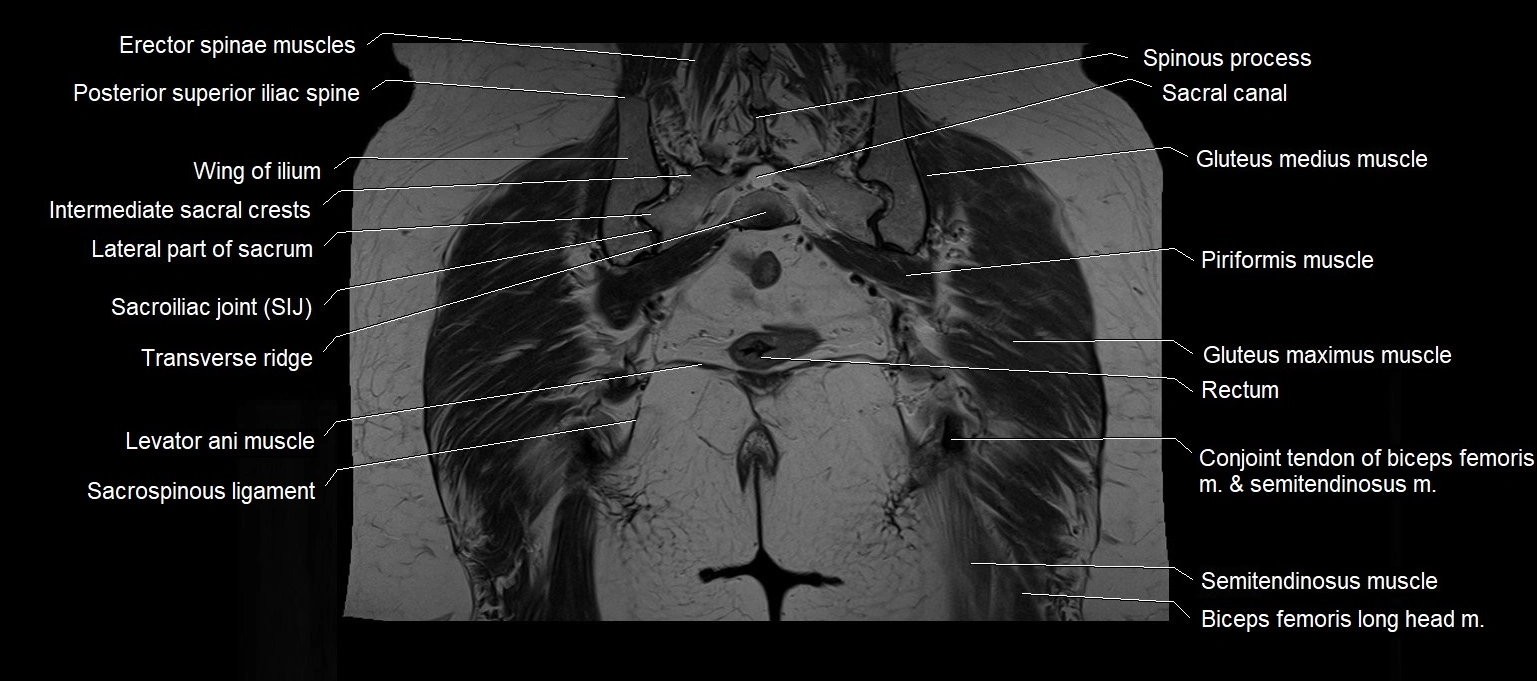

- Conjoint tendon of biceps femoris & semitendinosus

- Erector spinae muscles

- Intermediate sacral crest

- Lateral part of sacrum

- Levator ani muscle

- Piriformis muscle

- Posterior superior iliac spine

- Rectum

- Sacral canal

- Sacroiliac joint

- Sacrospinous ligament